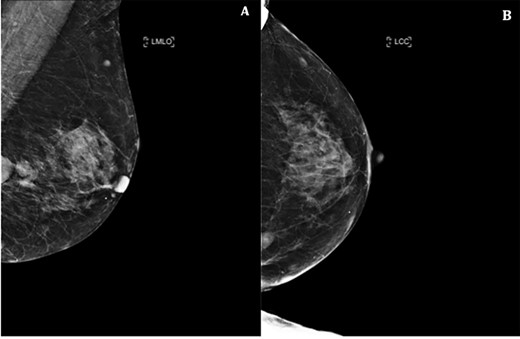

A. Left breast ultrasound showing two lesions at the 9 o’clock position measuring a total distance of 37 mm. B. Core biopsy done of the main lesion.

Triple assessment was done—examination revealed multiple cutaneous neurofibromas in keeping her NF1. Breast examination revealed a firm irregular 2-cm lump at the 9 o’clock position of the left breast with no contralateral lumps nor any evidence of lymphadenopathy. Bilateral mammogram demonstrated a dense indeterminate mass on the left breast (Fig. 1). Targeted ultrasound scan showed two cystic-like lesions adjacent to each other (Fig. 2). A core needle biopsy was done of the larger lesion confirming grade 3 invasive ductal carcinoma—receptor status analysis revealed that the lesion was ER negative, PR negative and HER2 positive.